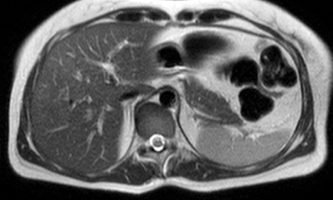

El estudio se complemento con resonancia magnética, donde se demostró la presencia de múltiples imágenes focales hepáticas confluentes con disminución de la señal en secuencias fuera de fase, no mostrando alteración de la señal en secuencias potenciadas en T2, sin signos de restricción al pulso difusión ni refuerzos anómalos luego de la administración de contraste endovenoso, estos hallazgos confirman la sospecha de esteatosis focal multinodular (fig. 5, 6 y 7).

En estos casos se recomienda realizar RM para confirmar la presencia de grasa en las “lesiones” identificadas y descartar otras etiologías, demostrando disminución de la señal en secuencias fuera de fase, sin alteración del pulso difusión (fig. 12 y 13).